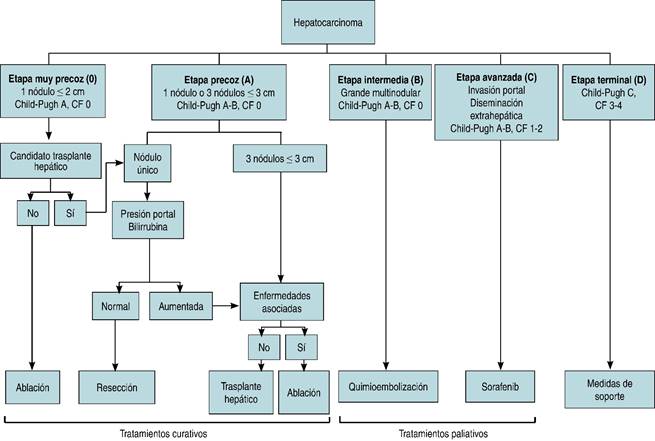

Existen diversas escalas en cuanto a la estadificación del carcinoma hepatocelular; no obstante, la clasificación BCLC (Barcelona Clinic Liver Cancer), tal como se describe en un artículo publicado en gastroenterología latinoamericana por Díaz y Barrera (Figura 1), tiene el mayor poder predictivo independiente de supervivencia, ya que incluye variables relacionadas con el tumor, además de la clasificación funcional hepática y la capacidad funcional del individuo que presenta dos enfermedades, tanto la cirrosis como el cáncer, y por último, la eficacia del tratamiento administrado.20

Figura 1: Clasificación y estrategias de tratamiento (adaptado de las guías de práctica clínica EASL-EORTC: manejo del carcinoma hepatocelular). Capacidad funcional (CF) entendida por 0 = sin síntomas; 1 = con síntomas leves, capaz de hacer actividad ligera; 2 = capaz de autocuidarse, pero no de trabajar; 3 = capacidad limitada de autocuidado, en cama o sentado > 50% del tiempo; 4 = dependiente, postrado.